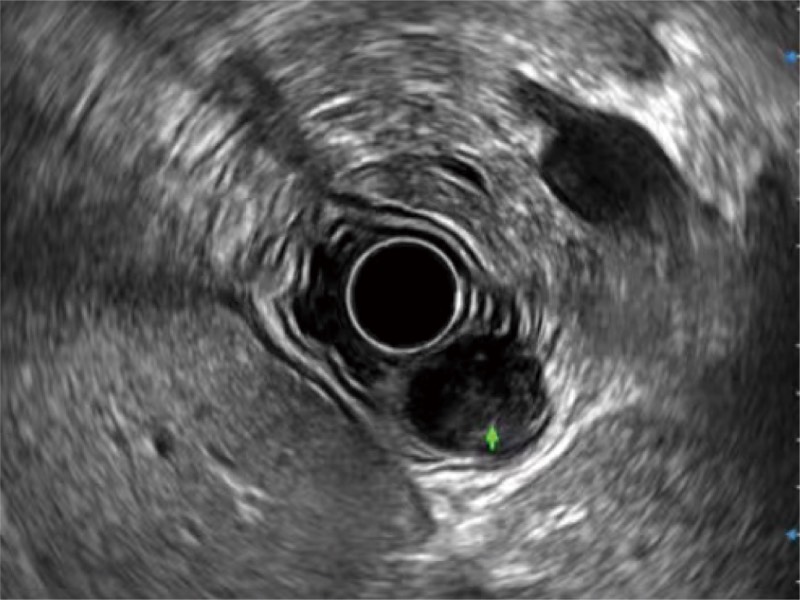

• 食管内间质瘤清晰显像

• 清晰显示胆总管及周围血管分布

• 肝左叶和肝静脉的横截面